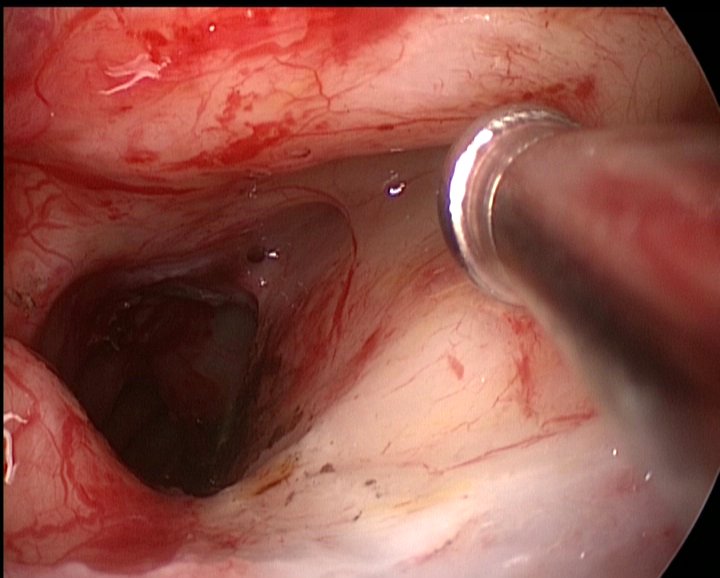

RMN cu substanţă de contrast efectuat postoperator confirmă existenţa unei restanțe tumorale cu un volum de aprox. 10% din volumul tumoral iniţial, situată în canalul nazofrontal stâng şi în sinusul frontal stâng (fig. 3).

Fig.3: RMN postoperator: restanta tumorala localizata in canalul nazofrontal stg